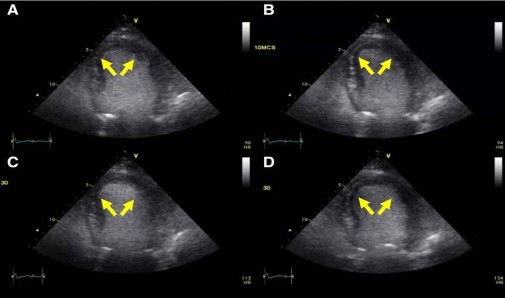

Siêu âm tim gắng sức với dobutamine là một công cụ chẩn đoán hình ảnh sẵn có để đánh giá tính sống còn cơ tim và dự trữ khả năng co bóp. Khi một đoạn của thành cơ tim không co bóp khi nghỉ, có thể truyền tĩnh mạch dobutamine liều thấp (2,5-10 µg/kg.phút) để tăng tính co bóp ở vùng cơ tim còn sống. Tiếp tục tăng dần liều dobutamine (10-40 µg/kg.phút) có thể dẫn đến những cải thiện tốt hơn trong tính co bóp hoặc ngược lại giảm vận động thành cơ tim theo vùng. Tình huống thứ hai được biết đến như là tình trạng đáp ứng hai pha với dobutamine, mà điều này tính chất dự đoán khả năng hồi phục của chức năng cơ tim sau tái tưới máu, với độ nhạy 76% và độ đặc hiệu 81% [33]. Hiện tượng này là biểu hiện của tăng lúc đầu dòng cấp máu mạch vành theo vùng kèm cải thiện tưới máu cơ tim và tính co bóp, theo sau đó là giai đoạn mất khả năng tiếp tục tăng dòng cấp máu đến cơ tim để đáp ứng nhu cầu oxy trong giai đoạn tăng liều dobutamine cao hơn. Sự cải thiện kéo dài của tính co bóp cơ tim trong thử nghiệm phân độ tăng dần tưới máu này cũng minh chứng cho vùng cơ tim còn sống bị thiếu máu cục bộ nhưng cũng có thể là đáp ứng bình thường trong bệnh cơ tim giãn nở không thiếu máu cục bộ.

Hình 1. 1: Siêu âm tim gắng sức với dobutamine có chất tương phản. Hình ảnh cuối thì tâm thu khi nghỉ: (A) liều thấp, (B) liều cao, (C) và

(D) đáp ứng hai pha với dobutamine ở vùng chi phối LAD (mũi tên).

“Nguồn: Garcia M. J. et al. (2020)”[53]